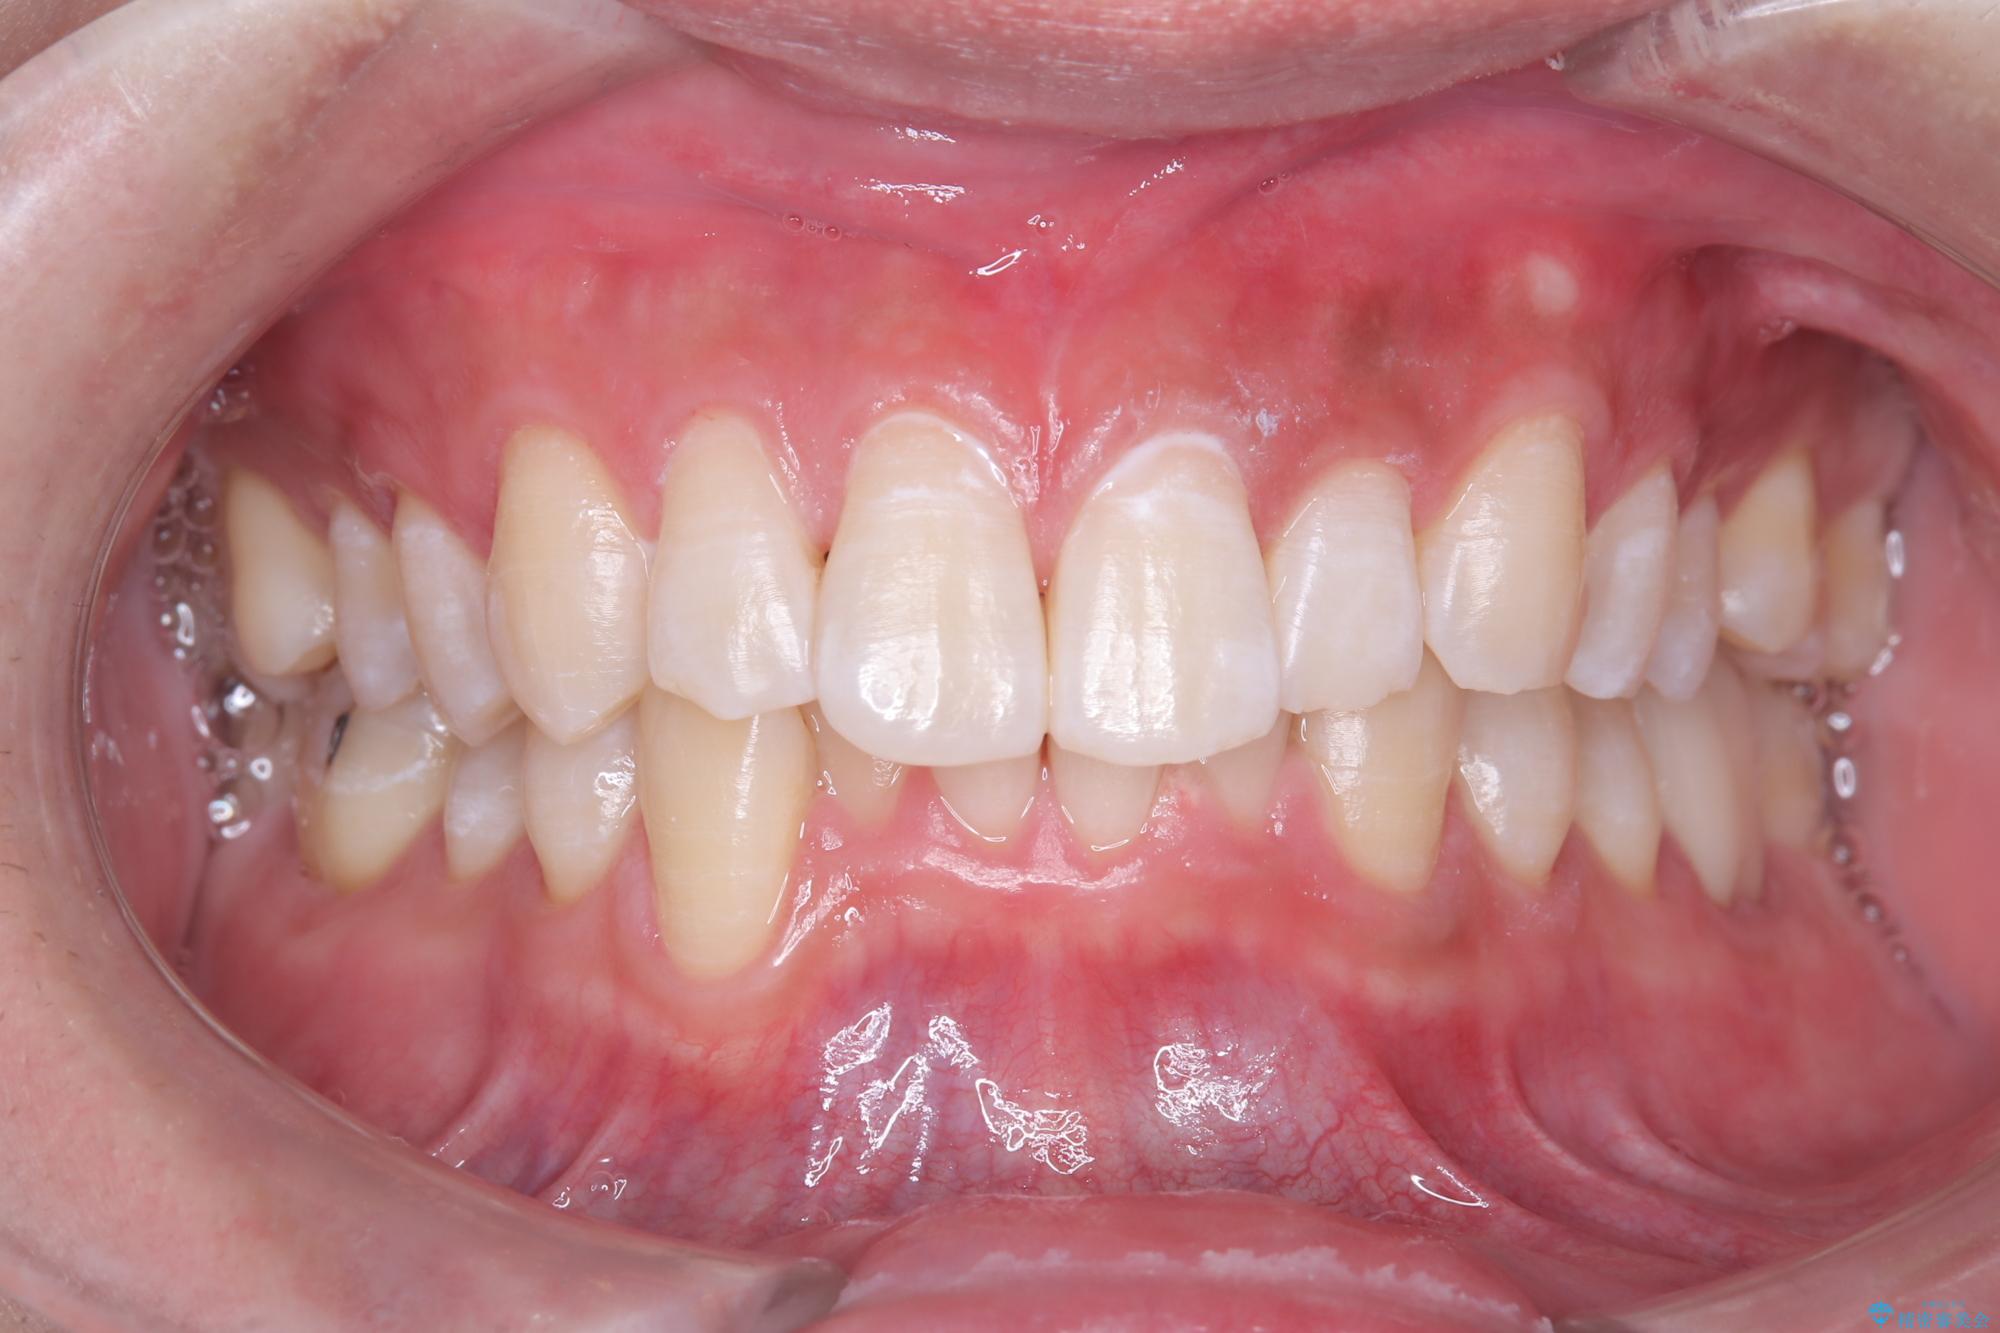

白い歯で清潔感get!初ホワイトニング

- 初めてのオフィスホワイトニングということで痛みなどの不安があったようですが、痛み等なくトーンアップし白くなりました。

ホワイトニングは色味が段々と後戻りしてきてしまうため、定期的に受けていただいたりホームホワイトニングと併用していただくと白さを保つことができます。